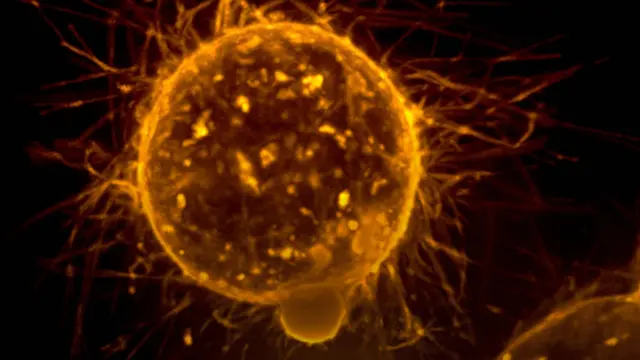

Las metástasis son responsables de más del 90 % de las muertes por cáncer, pero hasta ahora existen muy pocas terapias específicas para evitarlas.

El protagonista es el fármaco RA08, desarrollado por el VHIR y la empresa biotecnológica BCN Peptides, que actúa como inhibidor de una proteína, la integrina alfa9 (ITGA9), que es clave en el desarrollo de metástasis.

En ratones, los investigadores han observado que entre el 50 y el 70 % de los animales medicados no desarrollaban metástasis de dos de los cánceres infantiles más frecuentes: neuroblastoma, que ocurre cuando aparecen tumores en el tejido nervioso, y rabdomiosarcoma, cuando se originan en tejidos blandos, como los músculos.